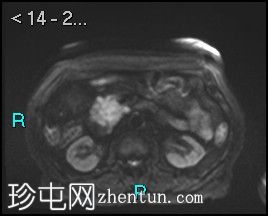

轴位

表观扩散系数 (ADC)

胰腺钩突附近可见边界不清的肿块,T2加权像呈不均匀中等信号,弥散受限明显。肿块大小为4.1 x 5 x 3 cm(前后径 x 横径 x 头尾径)。伴有胰管扩张,直径约6 mm。

肝脏可见多个大小不一的可疑病灶(从亚厘米级到2厘米不等)。T2加权像呈高信号,弥散受限明显。